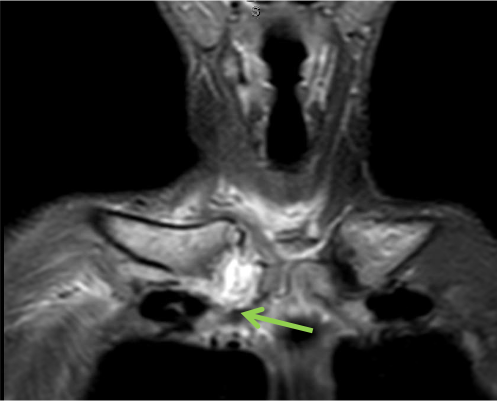

An MRI scan with contrast of the right sternoclavicular joint was suspect for right sternoclavicular septic arthritis with periarticular cellulitis/local myositis with local periclavicular adenopathy and possible evolving anterior mediastinitis. (Figures 1 and 2).

Results of a magnetic resonance imaging (MRI) scan with gadolinium of the right sternoclavicular joint were suspect for right sternoclavicular septic arthritis with periarticular cellulitis/local myositis with local periclavicular adenopathy and possible evolving anterior mediastinitis. At this point, the patient was referred to our ED for further evaluation.